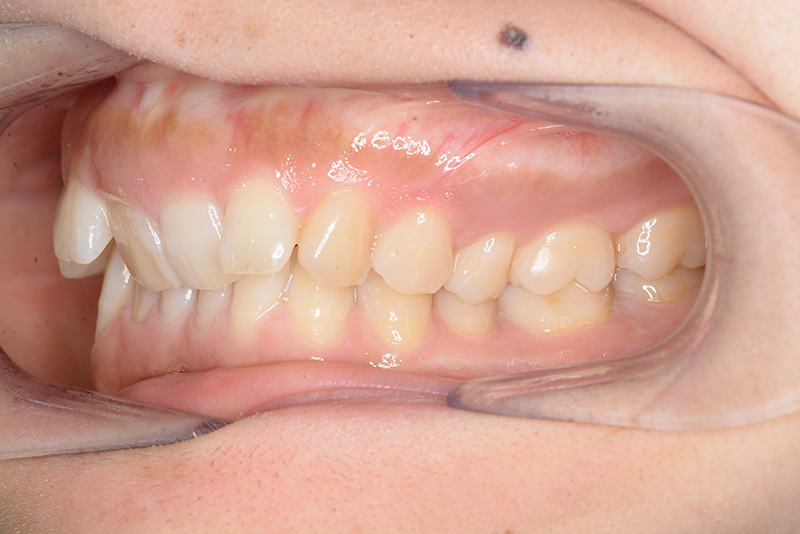

動的治療時(PLASによる上顎歯列遠心移動)

(PLASによる上顎歯列遠心移動)

批評・予后 上顎臼歯は軽度に近心傾斜しつつ、歯列遠心部には奥行きがあり、下顎歯列には叢生は認められず、スピー湾曲も軽度であること。また軟組織上の問題もないため、上顎歯列の遠心移動による治療が妥当だと判断した。治療後において上顎歯列の遠心傾斜と共に下顎はカウンタークロックワイズローテーションをしながら咬合の緊密化が得られた。